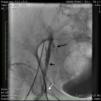

Case reportA 50-year-old Caucasian woman with hypertension, tobacco abuse, and peripheral arterial disease with life-limiting claudication had stents placed in bilateral 80% ostial iliac artery lesions two months previously. She was also noted to have a CTO of the left SFA at the ostium with no obvious stump (Figure 1) which was reconstituting distally via collaterals just above the popliteal artery (Figures 2 and 3). Due to her ongoing symptoms despite optimal medical therapy, it was decided to intervene on the SFA. Since there was no obvious stump of the occluded SFA proximally, we decided to approach the CTO through a retrograde approach.

An angiogram from the left femoral sheath at this time showed retrograde filling of the distal and proximal SFA (Figure 4) and then the dissection plane in the EIA with a wire tip perforation and bleeding (Figures 5 and 6) to the retroperitoneal region at the external iliac artery with displaced bladder (Figure 6). Protamine was given to reverse the heparin and a 7-minute balloon inflation was performed in the distal SFA using a 5.0 mm×40 mm Evercross balloon (ev3, Plymouth, MN) to stop the retrograde bleeding. On repeat angiography, the distal SFA CTO was reoccluded and the dissection plane appeared to be sealed, with no further bleeding into the retroperitoneal region (Figures 7 and 8). Other than mild nausea after protamine, the patient reported no major symptoms during this procedure. When activated coagulation time was 130 s, the femoral and popliteal sheaths were removed. A 3-g/dl drop in hemoglobin was noted after the procedure that remained stable over the next two days. Popliteal and pedal pulses were palpable and unchanged following the procedure.